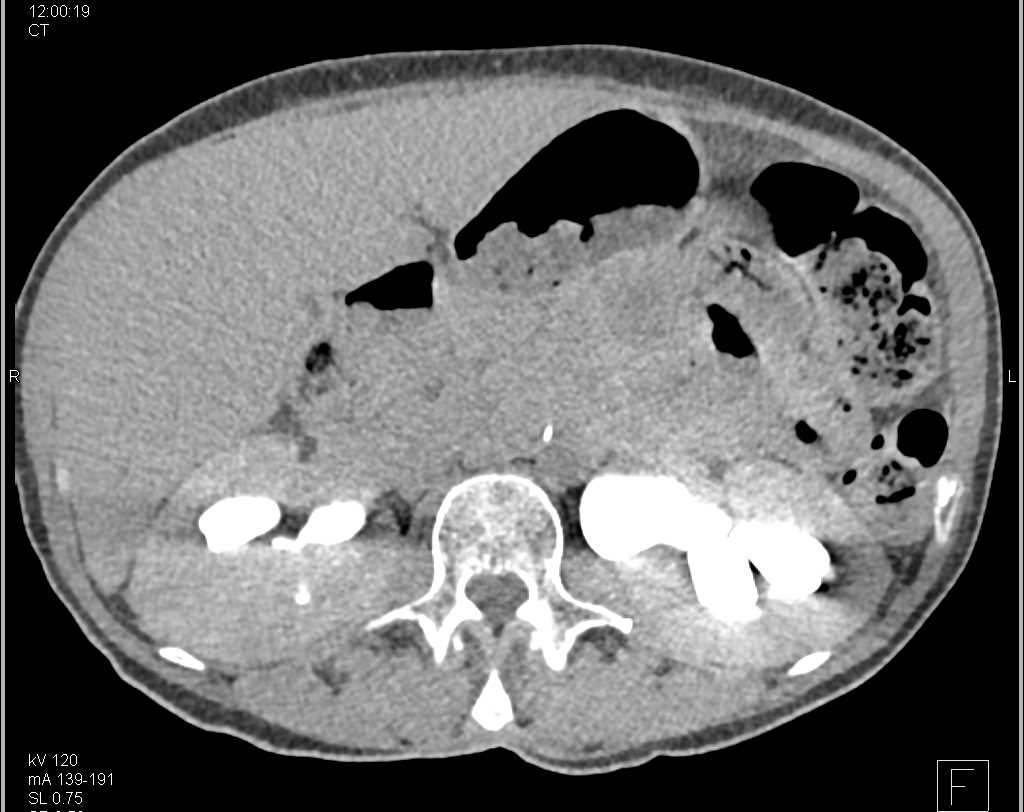

Renal Infarction in Patient with Vasculitis